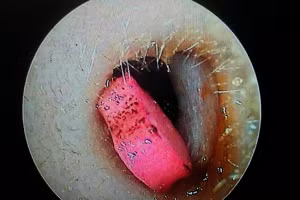

GD&TĐ - Ngày 30/9, tin từ Bệnh viện Đa khoa Trung ương Cần Thơ, các bác sĩ vừa lấy dị vật là hạt hồng xiêm bị bỏ quên nhiều năm trong người bệnh nhân.